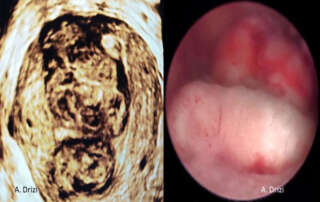

1) glandular island ectropion 2) micropolyps + hyperemia + edema

Diagnostic hysteroscopy: vagina and cervix. Micro-colpo-hysteroscopy